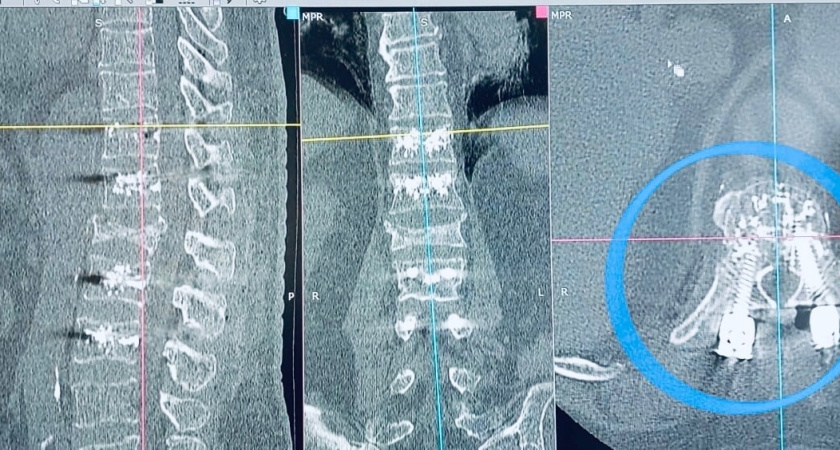

Как сообщили в пресс-службе БСМП, челнинские врачи провели уникальную операцию с «цементированием» позвоночника. 73-летний челнинец получил перелом в прошлом году. В результате остеопороза у мужчины начались жуткие боли. С такими жалобами он обратился к нейрохирургам. При помощи новейшей технологии free hand (свободные руки). Они установили в позвоночнике выполненные из титана восемь винтов размером 6,5х50 мм, которые скрепили между собой «цементом». Эти винты остаются в теле человека на всю жизнь. Организм их не отторгает, принимает. На следующий день после операции пациент начал ходить. Впереди – курс реабилитации. Мужчину уже выписали из больницы.